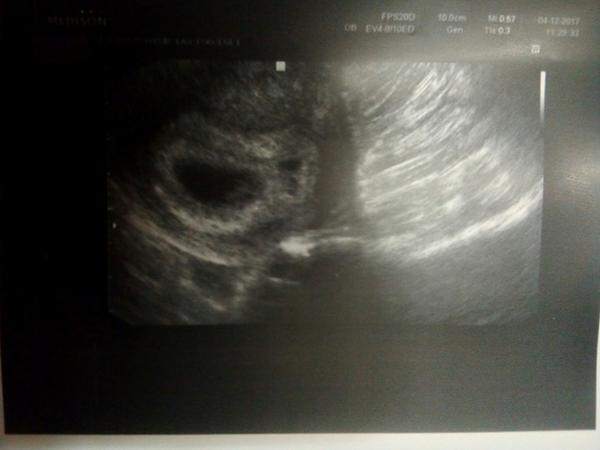

@volfici jj byly dve a moc dekuji. Jsme radi, ze alespon to jedno ❤